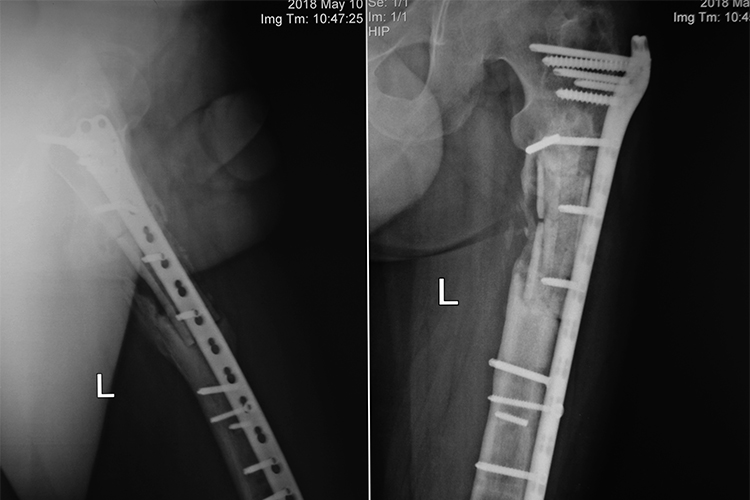

До нас знову завітав Ігор! Минулого тиждня молодий ветеран, боєць 28 окремої механізованої бригади відвідав ilaya для чергового огляду. Операції позаду, зараз триває активне відновлення стегнової кістки. На новому рентгенівському знімку добре помітно зміцнення кістки порівняно, навіть, зі знімком двомісячної давності. Кісткова мозоль також активно формується.

Це свіжий рентген, різниця порівняно з першим рентгеном разюча.